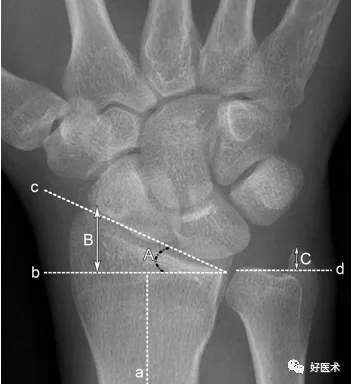

測量方法

a.橈骨縱軸線 b.橈骨縱軸線垂線 c.橈骨遠端關節面切線 d.尺骨遠端關節面水平線

A.橈骨內傾角 B.橈骨莖突長度 C.尺骨莖突長度

A.正常為15~35˚ 。若此角度改變,提示橈骨遠端骨折或腕關節脫位。

B.正常為8~18mm,且橈骨莖突較尺骨莖突低1~1.5cm。若此長度改變,提示橈骨遠端骨折。

C.正常為2~8mm。若此長度改變,提示尺骨莖突骨折或尺骨莖突過長(尺骨莖突撞擊綜合症)